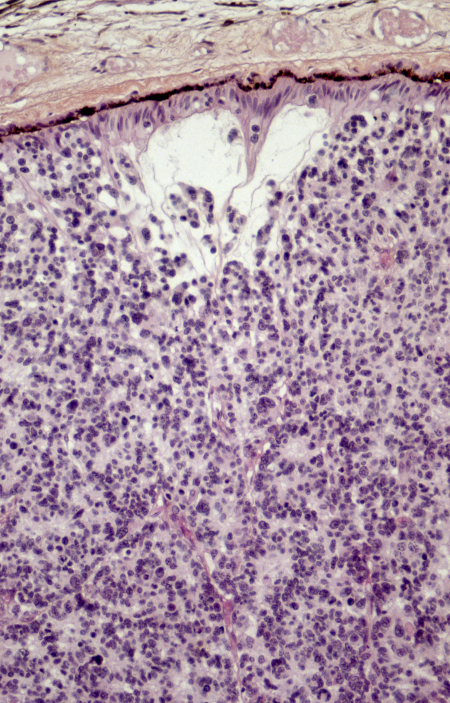

[Figure caption and citation for the preceding image starts]: Histopatologia do retinoblastoma. Esta imagem demonstra as características clássicas do retinoblastoma, incluindo células tumorais pequenas, arredondadas e densamente concentradas, com núcleos hipercromáticos e citoplasma escasso, dispostas em camadas. A ausência de rosetas de Flexner-Wintersteiner nesta amostra não impede o diagnóstico, pois sua presença não é obrigatória. Essas características histopatológicas são típicas desse tumor retiniano agressivo e fornecem informações críticas para o diagnóstico, o estadiamento e o prognósticoPR J. L. Kemeny, ISM/Science Photo Library; usado com permissão [Citation ends].

[Figure caption and citation for the preceding image starts]: Micrografia óptica de um corte da retina de um paciente com retinoblastoma, uma forma rara de câncer intraocular. O tumor apresenta uma arquitetura retiniana alterada e crescimento infiltrante de células atípicas. A imuno-histoquímica com anticorpos anti-rodopsina destaca áreas de diferenciação de fotorreceptores preservadas dentro do tecido retiniano. Essa coloração auxilia na identificação das camadas residuais da retina em meio à proliferação celular malignaPR J. L. Kemeny, ISM/Science Photo Library; usado com permissão [Citation ends].